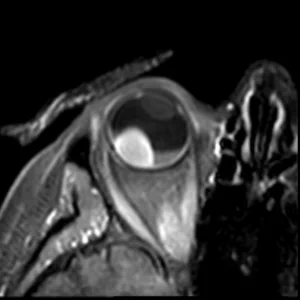

Obl

The orientation of multi-slice scans is tailored to the location and geometry of the tumour. It is typically perpendicular to the sclera and chosen such that the lesion and associated pathology are visualized in one slice.

For patients with complex pathology, e.g. both retinal detachment and optic nerve invasion, we perform these scans twice with different orientations.